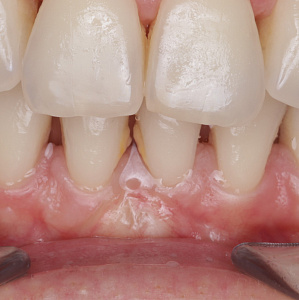

Гингивит

Гингивит проявляется отёчностью, болезненностью и кровоточивостью дёсен, большим количеством мягкого зубного налёта, гнилостным запахом изо рта. Возможно также увеличение межзубных промежутков и зубная боль. Основная причина появления гингивита – это недостаточная гигиена ротовой полости, формирование зубного налёта, наличие кариеса. К факторам риска также относятся диабет, дефицит витамина С, некачественное питание, зубочелюстные аномалии, механические травмы.